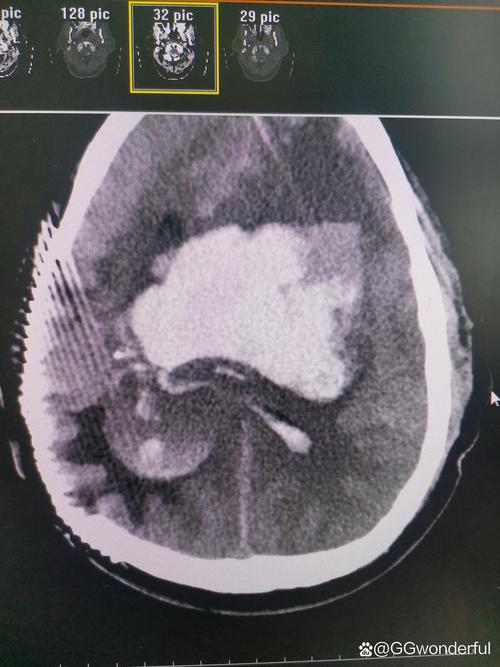

脑梗后脑子又有新出血

(图片来源网络,侵删)